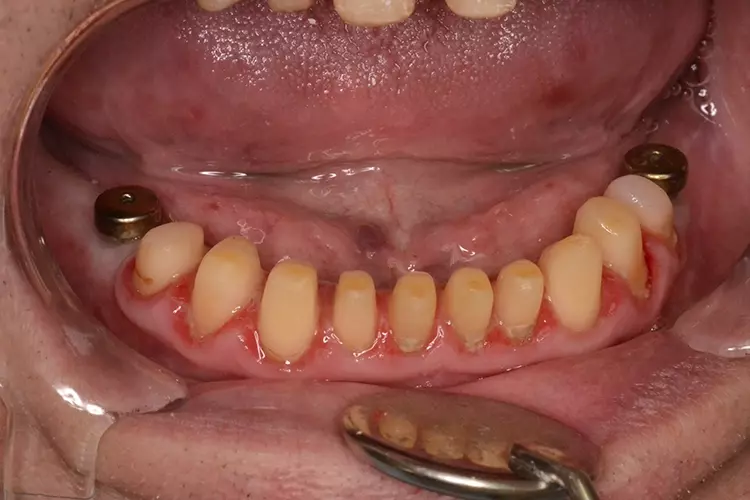

Neugestaltung der Front bei starken Zahnfehlstellungen

Bei dem heute 49-jährigen Patienten wurde seit Kindertagen versäumt, die Ober- und Unterkieferzahnbögen kieferorthopädisch auszurichten. Der Patient leidet seitdem stark unter seinen Zahnfehlstellungen.

Die Fraktur des stark elongierten Zahnes 21 war für den Patienten der Ausgangspunkt, sowohl die Front des Ober- als auch des Unterkiefers prothetisch überarbeiten zu lassen. Dabei wurde der frakturierte Zahn 21 durch ein navigiert eingesetztes Sofortimplantat ersetzt, während die verschachtelt stehenden Zähne 12 und 42 durch eine Brückenversorgung korrigiert wurden (Abb. 4a-j).